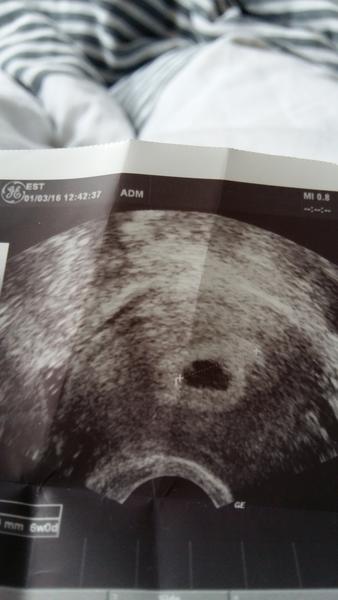

Ahojda, holky, nemáte někdo prosím zkušenost s prázdným gestačním váčkem, v 5tt- 6tt?

@victoireux u mě rostl především gestační váček, miminko (nechci psát embryo ☹ ) odpovídalo začátku sedmého tt.

@pipulka: Určitě je všechno v pořádku. Já měla stejný váček v 5+1, v 7+1 už bylo vidět miminko i srdíčko. Hlavně buď v klidu! A pokud tě doktor vylekal (někteří to umí skvěle), zkus myslet pozitivně. V prvních týdnech se to mění hrozně rychle - dneska tam miminko není, za pár dní už je. Myslím, že příště už vykoukne 🙂 ... jak jsi na tom s cyklem? Máš ho pravidelný, nebo delší? Někdy se stává, že žena otěhotní později, pak je těhotenství mladší, nevychází "podle tabulek" a někteří doktoři se z toho mohou zbláznit 🙂 (můj případ)